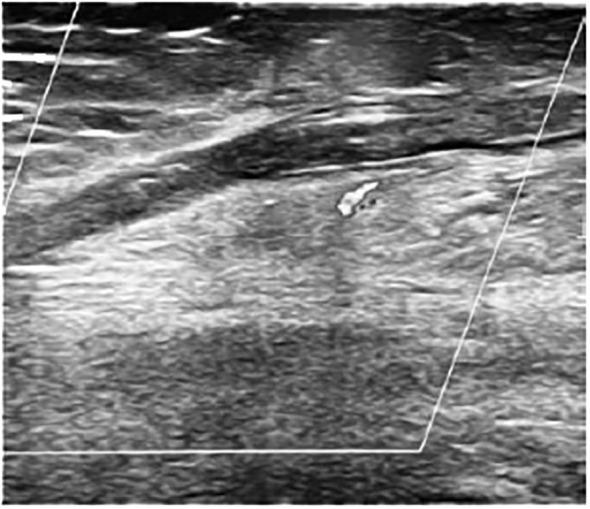

Five patients (26.3%) presented vascular events, which all occurred in connection with sodium imbalances. Three DVT (two with associated pulmonary embolism, in one case leading to death) developed in the post-operative period, most frequently at 7-10 days. Elevated D-dimers, a reduced partial activated thrombin time and a prolonged C-reactive protein increase were highly related to thrombotic vascular events. One case of posterior cerebral artery pseudoaneurysm was described soon after neurosurgery, requiring vascular stenting. Superficial vein thrombophlebitis was a late complication in one patient with other predisposing factors.

5 名患者(26.3%)出现血管事件,这些事件均与钠失衡有关。3 例 DVT(其中 2 例合并肺栓塞,1 例导致死亡)发生在术后,最常发生在术后 7-10 天。升高的 D-二聚体、部分激活的凝血酶时间缩短和 C 反应蛋白升高延长与血栓性血管事件高度相关。1 例术后不久即出现大脑后动脉假性动脉瘤,需要血管支架置入。1 例有其他诱发因素的患者出现浅表静脉血栓性静脉炎的晚期并发症。